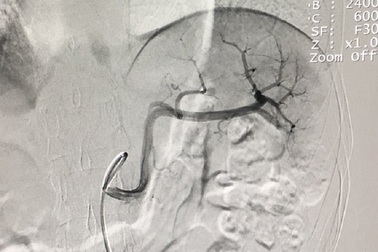

Gây tắc động mạch cứu lá lách bị vỡ cho cô gái trẻNhập viện trong tình trạng đau nhiều ở vùng hạ sườn trái sau tai nạn giao thông, bác sĩ phát hiện cô gái trẻ bị vỡ lạch đe dọa tính mạng. Nữ bệnh nhân đã được can thiệp gây tắc động mạch, bảo tồn được lá lách vỡ.